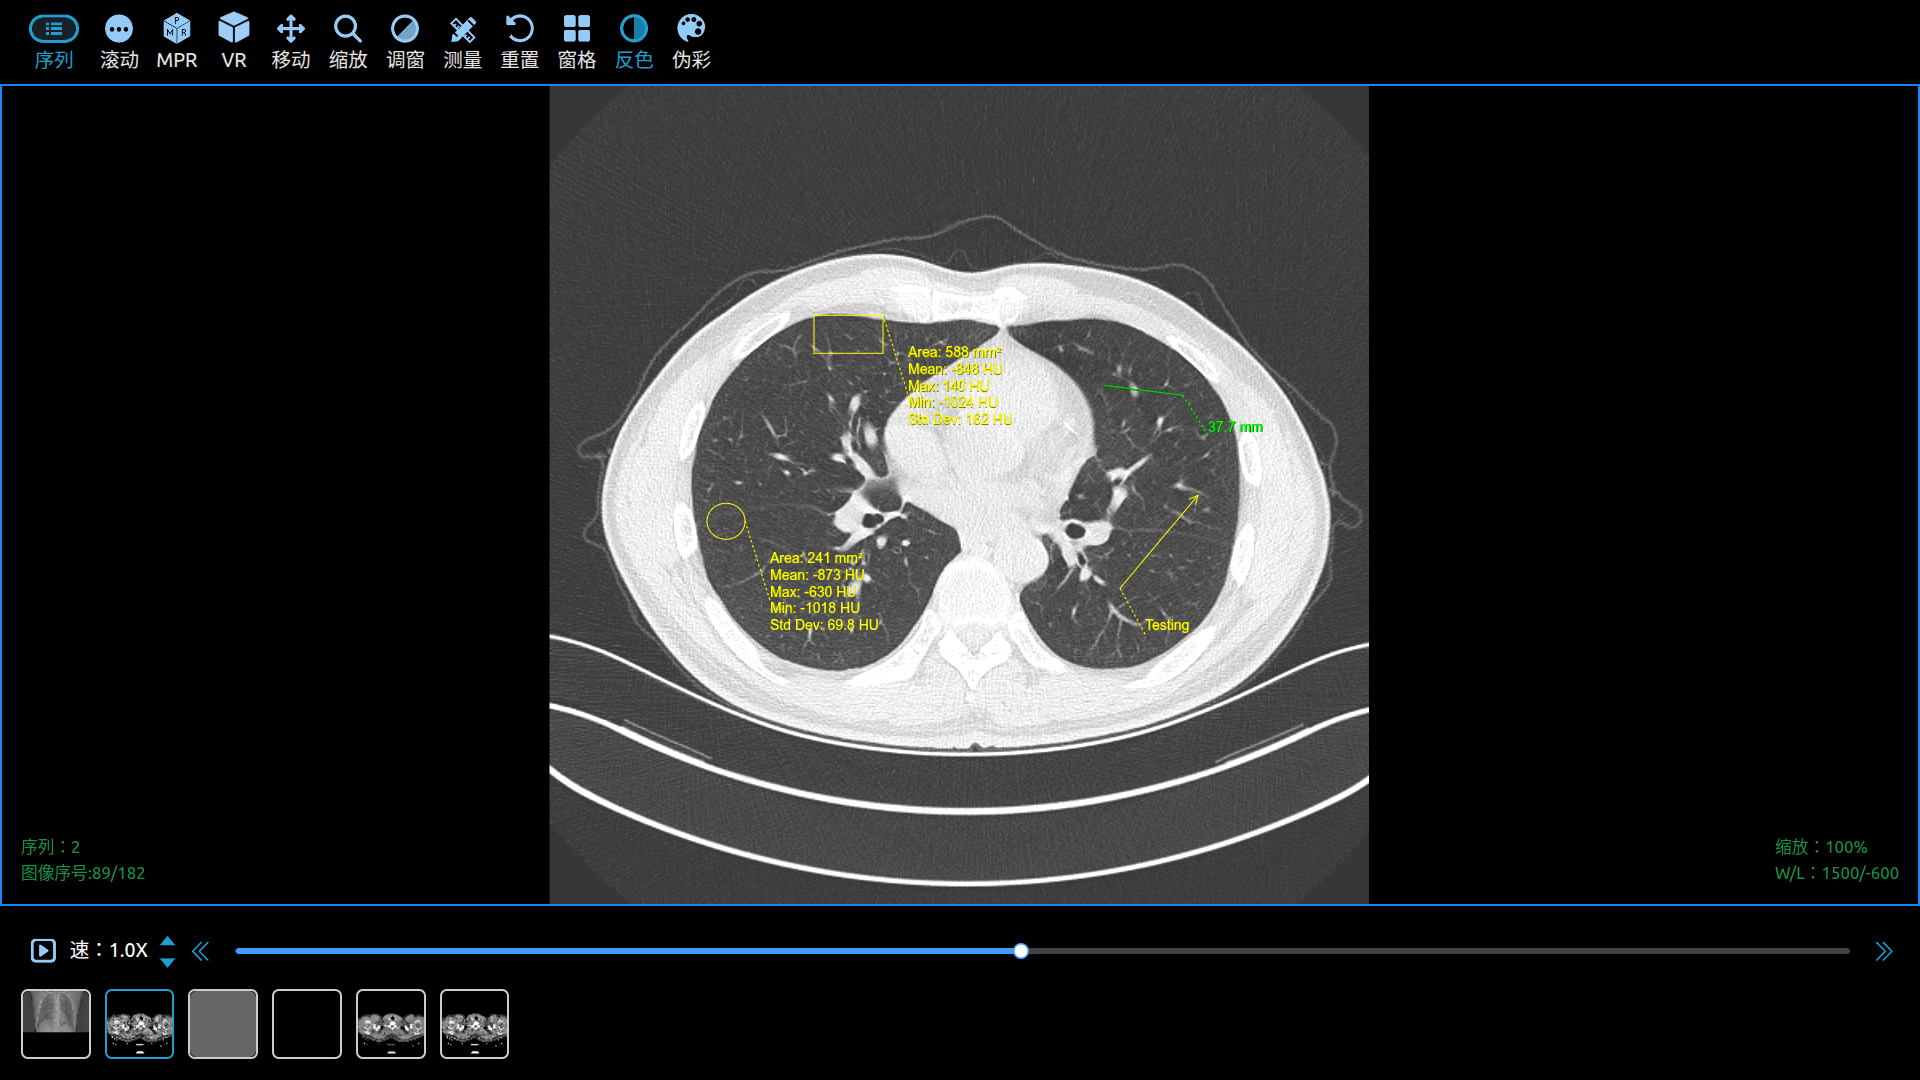

Use Cornerstone3D to View DICOM Images in a Web Browser.